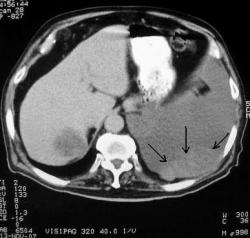

Слева на париетальной плевре овально-вытянутой формы образование, плохо дифференцирующееся на фоне жидкости (плотность образования 30ед, а жидкости 20-25ед). В правой доле печени солитарный метастаз, укрепивший в мысли о мезотелиоме плевры.

Стрелками обозначено объемное образование, оно плохо видно из-за высокой плотности жидкости (при пункции геморрагическая жидкость), васкуляризировано слабо, но всё же накапливает контрастное вещество.